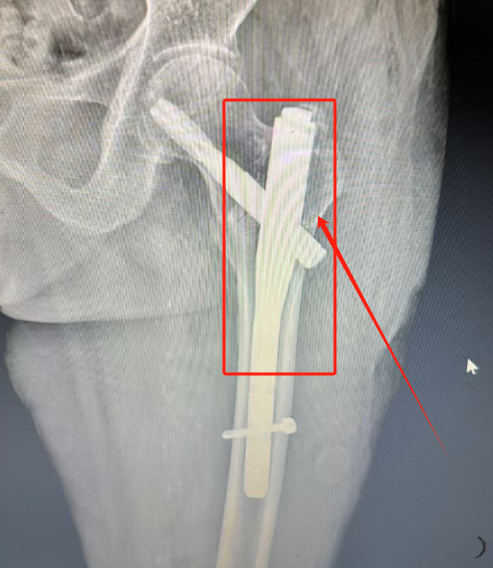

骨科(创伤中心)负责人韩雪峰团队针对王奶奶年事已高,基础性疾病多,心脑肺储备功能差等病情,进行充分的术前评估,制定周密手术方案,在椎管内麻醉下行股骨转子间骨折闭合复位髓腔钉内固定术,手术非常成功。

术后第二天,王奶奶在管床医生周成彬指导、协助下使用助行器下地行走。